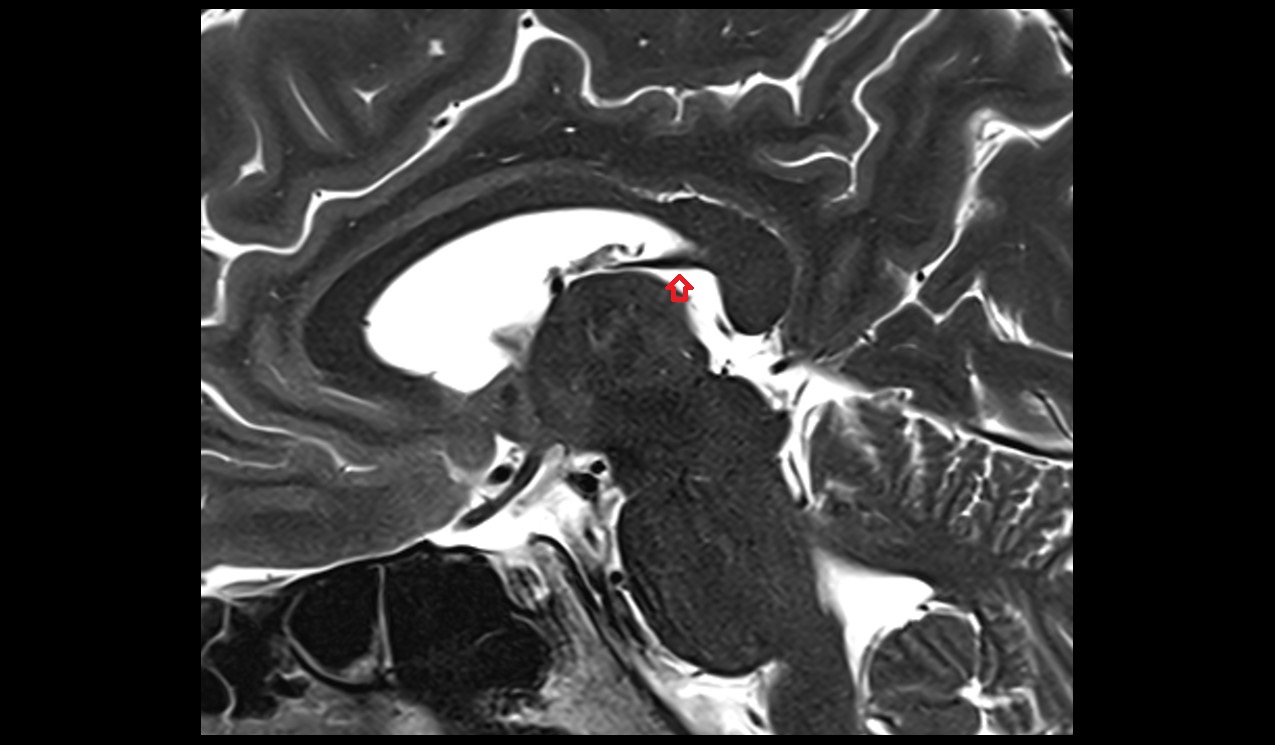

- Meckel’s cave (Trigeminal cave)

- Trigeminal cave